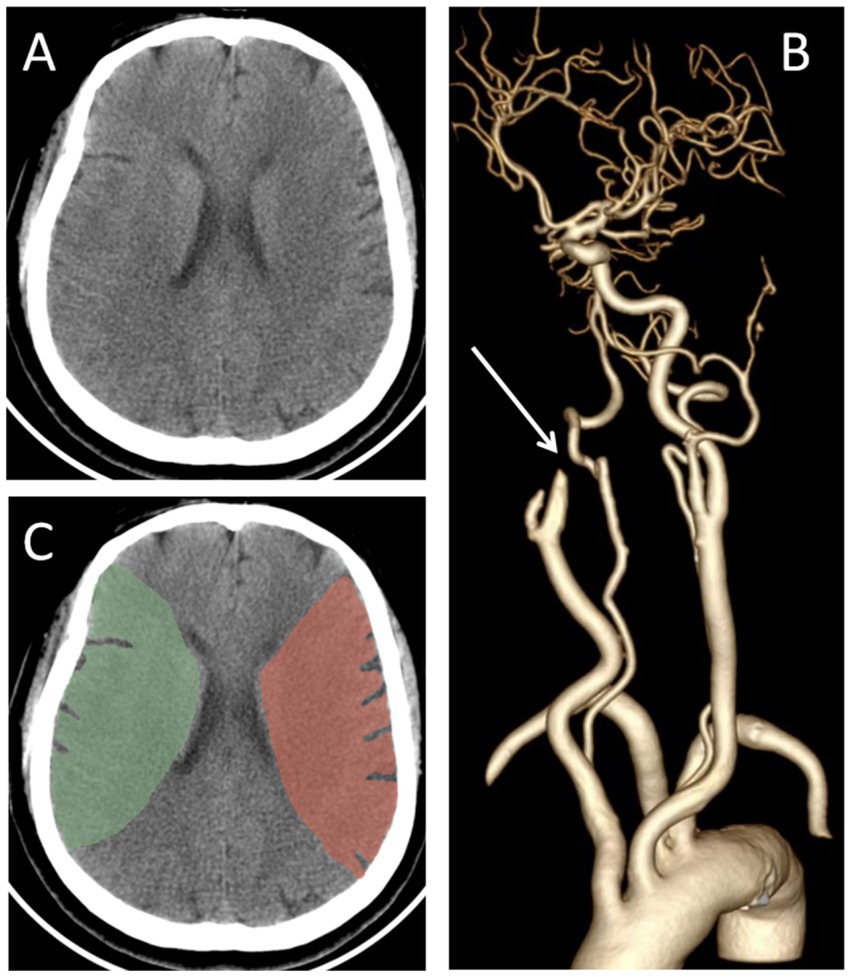

Before EVT, all participants underwent cranial CT, CT angiography and CT perfusion imaging, and underwent follow-up cranial CT scans at 24 h, 3 days, and 7 days after EVT. Additional cranial CT scans were performed immediately if participants developed deterioration in consciousness or clinical neurological status. Based on the admission cranial CT imaging, the NWU in the affected middle cerebral artery territory was measured by using the Segment Editor module of 3D Slicer software. Firstly, the bilateral middle cerebral artery territories were delineated. The anterior boundary was defined by the extension line of the anterior horn of the lateral ventricle, while the posterior boundary was defined by the extension line of the posterior horn of the lateral ventricle. The outer boundary followed the cerebral cortex margin, and the inner boundary was marked by the medial edge of the caudate nucleus and the posterior limb of the internal capsule (Figure 1). Subsequently, the Radiomics module was employed to automatically acquire the parenchymal density values of bilateral middle cerebral artery territories. The NWU was calculated by (1- density of affected territory/density of contralateral territory) × 100% (22).

Figure 1. Representative cases of the NWU measurement. (A) The preoperative cranial CT of a ALVOS patient; (B) the CT angiography showed the occlusion of the right internal carotid artery; (C) the NWU was calculated by (1- density of affected territory[green region]/density of contralateral territory[red region]) × 100%. ALVOS indicates acute large vessel occlusion stroke; NWU, net water uptake.